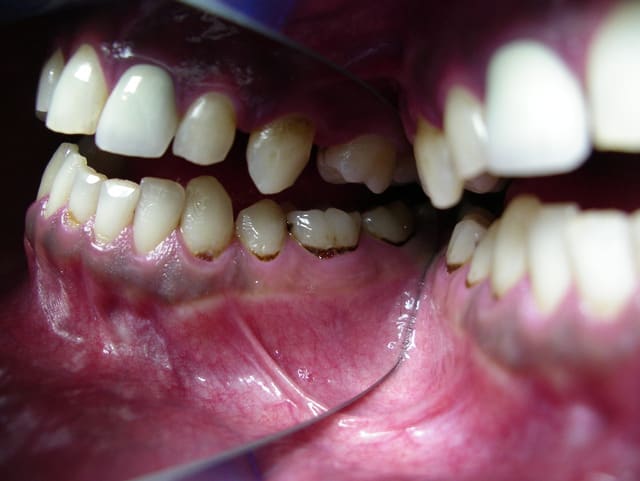

Déjà il faut savoir que la méthadone est TRES sucrée. Donc cela augmente le risque de carie chez des patients dont on sait déjà que l'hygiène n'est pas là et où il y a déjà beaucoup de caries.

Ensuite, effectivement, les réactions aux anesthésies sont plus longues. Les caries se développent rapidement avec énormément de caries du collet.

la carie de Lowenthal serait pathognomonique de la consommation d'héroïne

en avez vous déjà constaté? quelle est cette forme clinique spécifique?